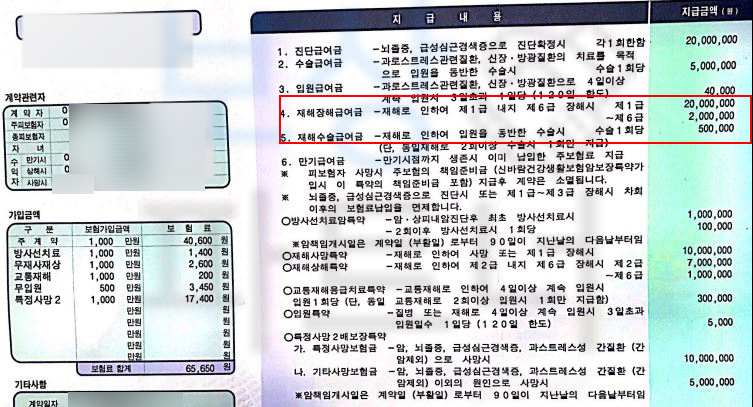

위 진단으로 이@@님은 최소 10주간 TLSO 보조기 즉 허리보조기를 착용하시며 요양하셔야 했습니다. 여러분들의 보험증권에 “후유장해” 항목 찾아보세요. 위 보험증권들을 보면 가입하신 보험의 기본계약에 있거나 혹은 특약으로 후유장해 보상 항목이 있습니다.

저희는 의뢰인의 장해보험금 청구를 위해

공신력있는 타 병원의 전문의로부터

AMA 방식의 후유장해 평가를 진행하였고

그 결과

무려** 30%의 지급률 뚜렷한 기형**에 해당하셨습니다. 저희는 이를 기초로 손해사정서와 각종 증빙서류를 제출하였습니다. 물론 보험사에서는 이전의 질병들을 조회하며 골다공증의 여부와 각도와 압박률의 적절성에 대해 의료자문을 시행했지만 보상파트너의 적절한 대응으로 결국 저희가 처음 청구한 30% 지급률 인정되어

후유장해보험금 2,700만원

전액 보상되었습니다.